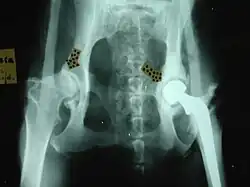

Orthopedic surgery

Common orthopedic surgeries in animals include:

- Ruptured cranial cruciate ligament repair

- For hip dysplasia:

- Femoral head osteotomy

- Triple pelvic osteotomy

- Hip replacement

- Leg amputation

- Bone fracture repair

- Arthroscopy

- MPL - medial patellar luxation